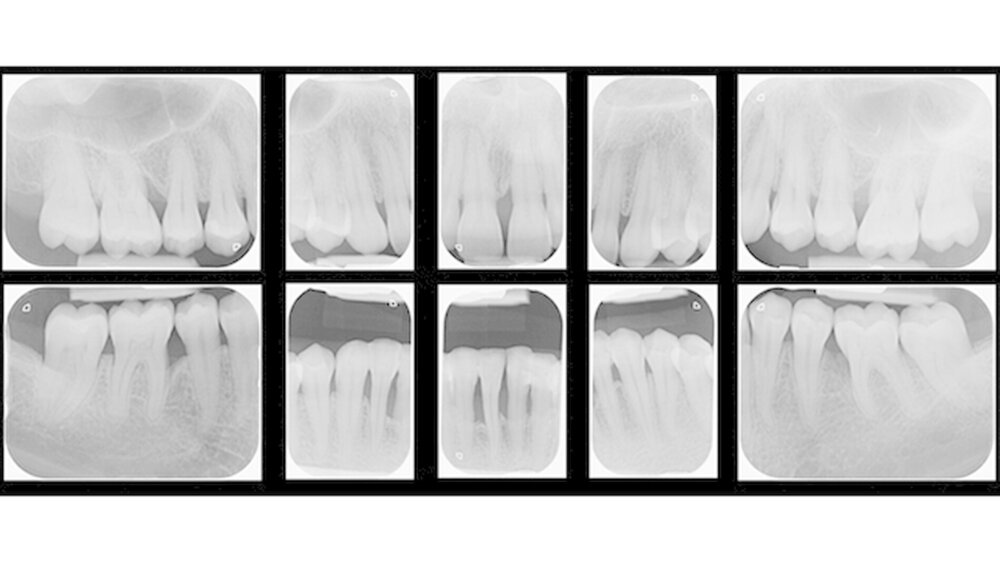

Neben stabilen klinischen Parametern fanden wir zehn Jahre nach APT ebenfalls eine stabile orale Mikroflora mit geringen Leveln der Parodontalpathogene A.actinomycetemcomitans, P.gingivalis, T.forsythia und T.denticola bei Patienten mit AgP vor. Es zeigte sich, dass die adjuvante Antibiotikagabe parallel zur APT A.actinomycetemcomitans langfristig supprimieren kann. Dies muss jedoch aufgrund der geringen Fallzahl in weiteren Studien untersucht werden.

Die prognostische Aussagekraft der modifizierten PRB nach Lang & Tonetti (2003) im Rahmen der UPT konnte für die AgP nicht bestätigt werden. Die Anwendung der PRB scheint durch Überschätzung des individuellen Risikoprofils bei Patienten mit AgP zu einer Überversorgung zu führen. Durch Herausnahme des Faktors IL-1ß-Polymorphismus steigt jedoch die Voraussagekraft des PRB-Models und ist in der Lage, Patienten nach ihrem Risikoprofil eindeutig zu klassifizieren.